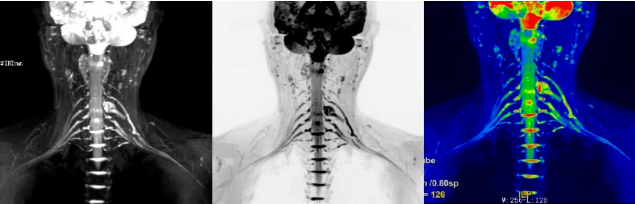

病例

术后复查